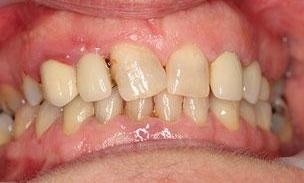

The patient wanted to be able to smile when she retires and travels around. An infected upper incisor was removed before a carefully designed ceramic bridge and a crown were placed. She was so thrilled with the result! Now she can show her teeth when she smiles in her photos.